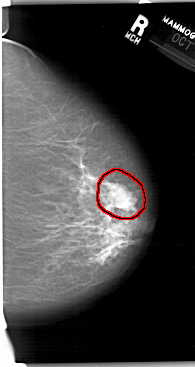

FILE: A_1411_1.RIGHT_CC.OVERLAY

TOTAL_ABNORMALITIES 1

ABNORMALITY 1

LESION_TYPE MASS SHAPE LOBULATED MARGINS MICROLOBULATED

ASSESSMENT 4

SUBTLETY 4

PATHOLOGY BENIGN

TOTAL_OUTLINES 1

BOUNDARY